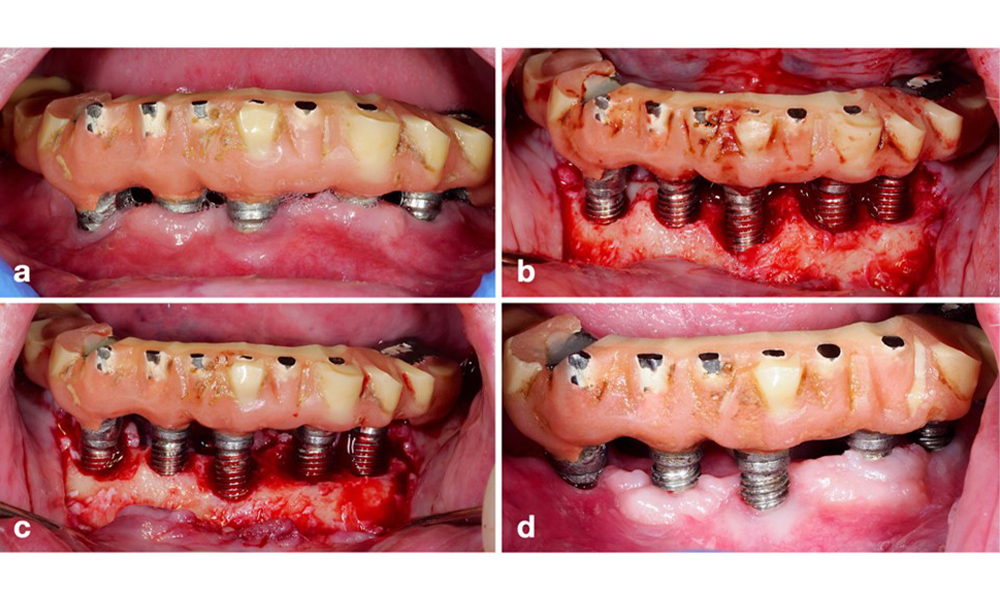

Periimplantitis ist zu erkennen an (1) Entzündungszeichen, vergleichbar einer Mukositis, (2) einem radiologischen Nachweis von Knochenverlust nach Ersteinheilung und (3) der Zunahme der Sondierungstiefe im Vergleich zu Messungen kurz nach dem Einsetzen der prothetischen Rekonstruktion (Abb. 2). Liegen keine früheren Röntgenaufnahmen vor, weisen ein radiologisches Knochenniveau von ≥ 3 mm zusammen mit Sondierungsblutungen und Sondierungstiefen von ≥ 6 mm auf eine Periimplantitis hin.

Restaurationen des gesamten Zahnbogens mit unterschiedlichem Grad der Periimplantitis bei einigen der Implantate. Das Implantat an Position 21 ist mit Sondierungstiefen von bis zu 9 mm (a), Sondierungsblutung, Eiterbildung am periimplantären Sulkus und einer vestibulären Fistel (b-c) stark betroffen. Die Röntgenaufnahme zeigt einen Knochenverlust von etwa 50 % für das Implantat mit Periimplantitis an Position 21, während das Implantat an Position 23 nur einen begrenzten Knochenverlust aufweist, entsprechend etwa dem, was bei Implantaten dieses Typs nach der Ersteinheilung zu erwarten ist (d).

Abb. 2. Restaurationen des gesamten Zahnbogens mit unterschiedlichem Grad der Periimplantitis bei einigen der Implantate. Das Implantat an Position 21 ist mit Sondierungstiefen von bis zu 9 mm (a), Sondierungsblutung, Eiterbildung am periimplantären Sulkus und einer vestibulären Fistel (b-c) stark betroffen. Die Röntgenaufnahme zeigt einen Knochenverlust von etwa 50 % für das Implantat mit Periimplantitis an Position 21, während das Implantat an Position 23 nur einen begrenzten Knochenverlust aufweist, entsprechend etwa dem, was bei Implantaten dieses Typs nach der Ersteinheilung zu erwarten ist (d).